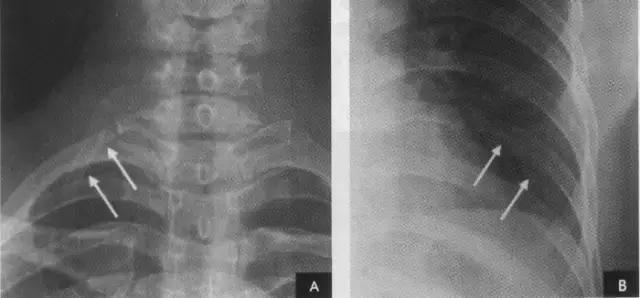

2、横裂又称水平裂,约70%的人正、撼位胸片均可显影。在正位片上表现为右中肺野横行细线状阴影,从第6肋腋部水平自外向内延伸.并止于肺门外lcm处。可向上或向下倾斜10:左右或略成曲线;在侧位片上,横裂起白斜裂中部,向前呈水平方向走行达前胸壁。其位置的改变可作为判断肺体积变化的标志(如上图)。